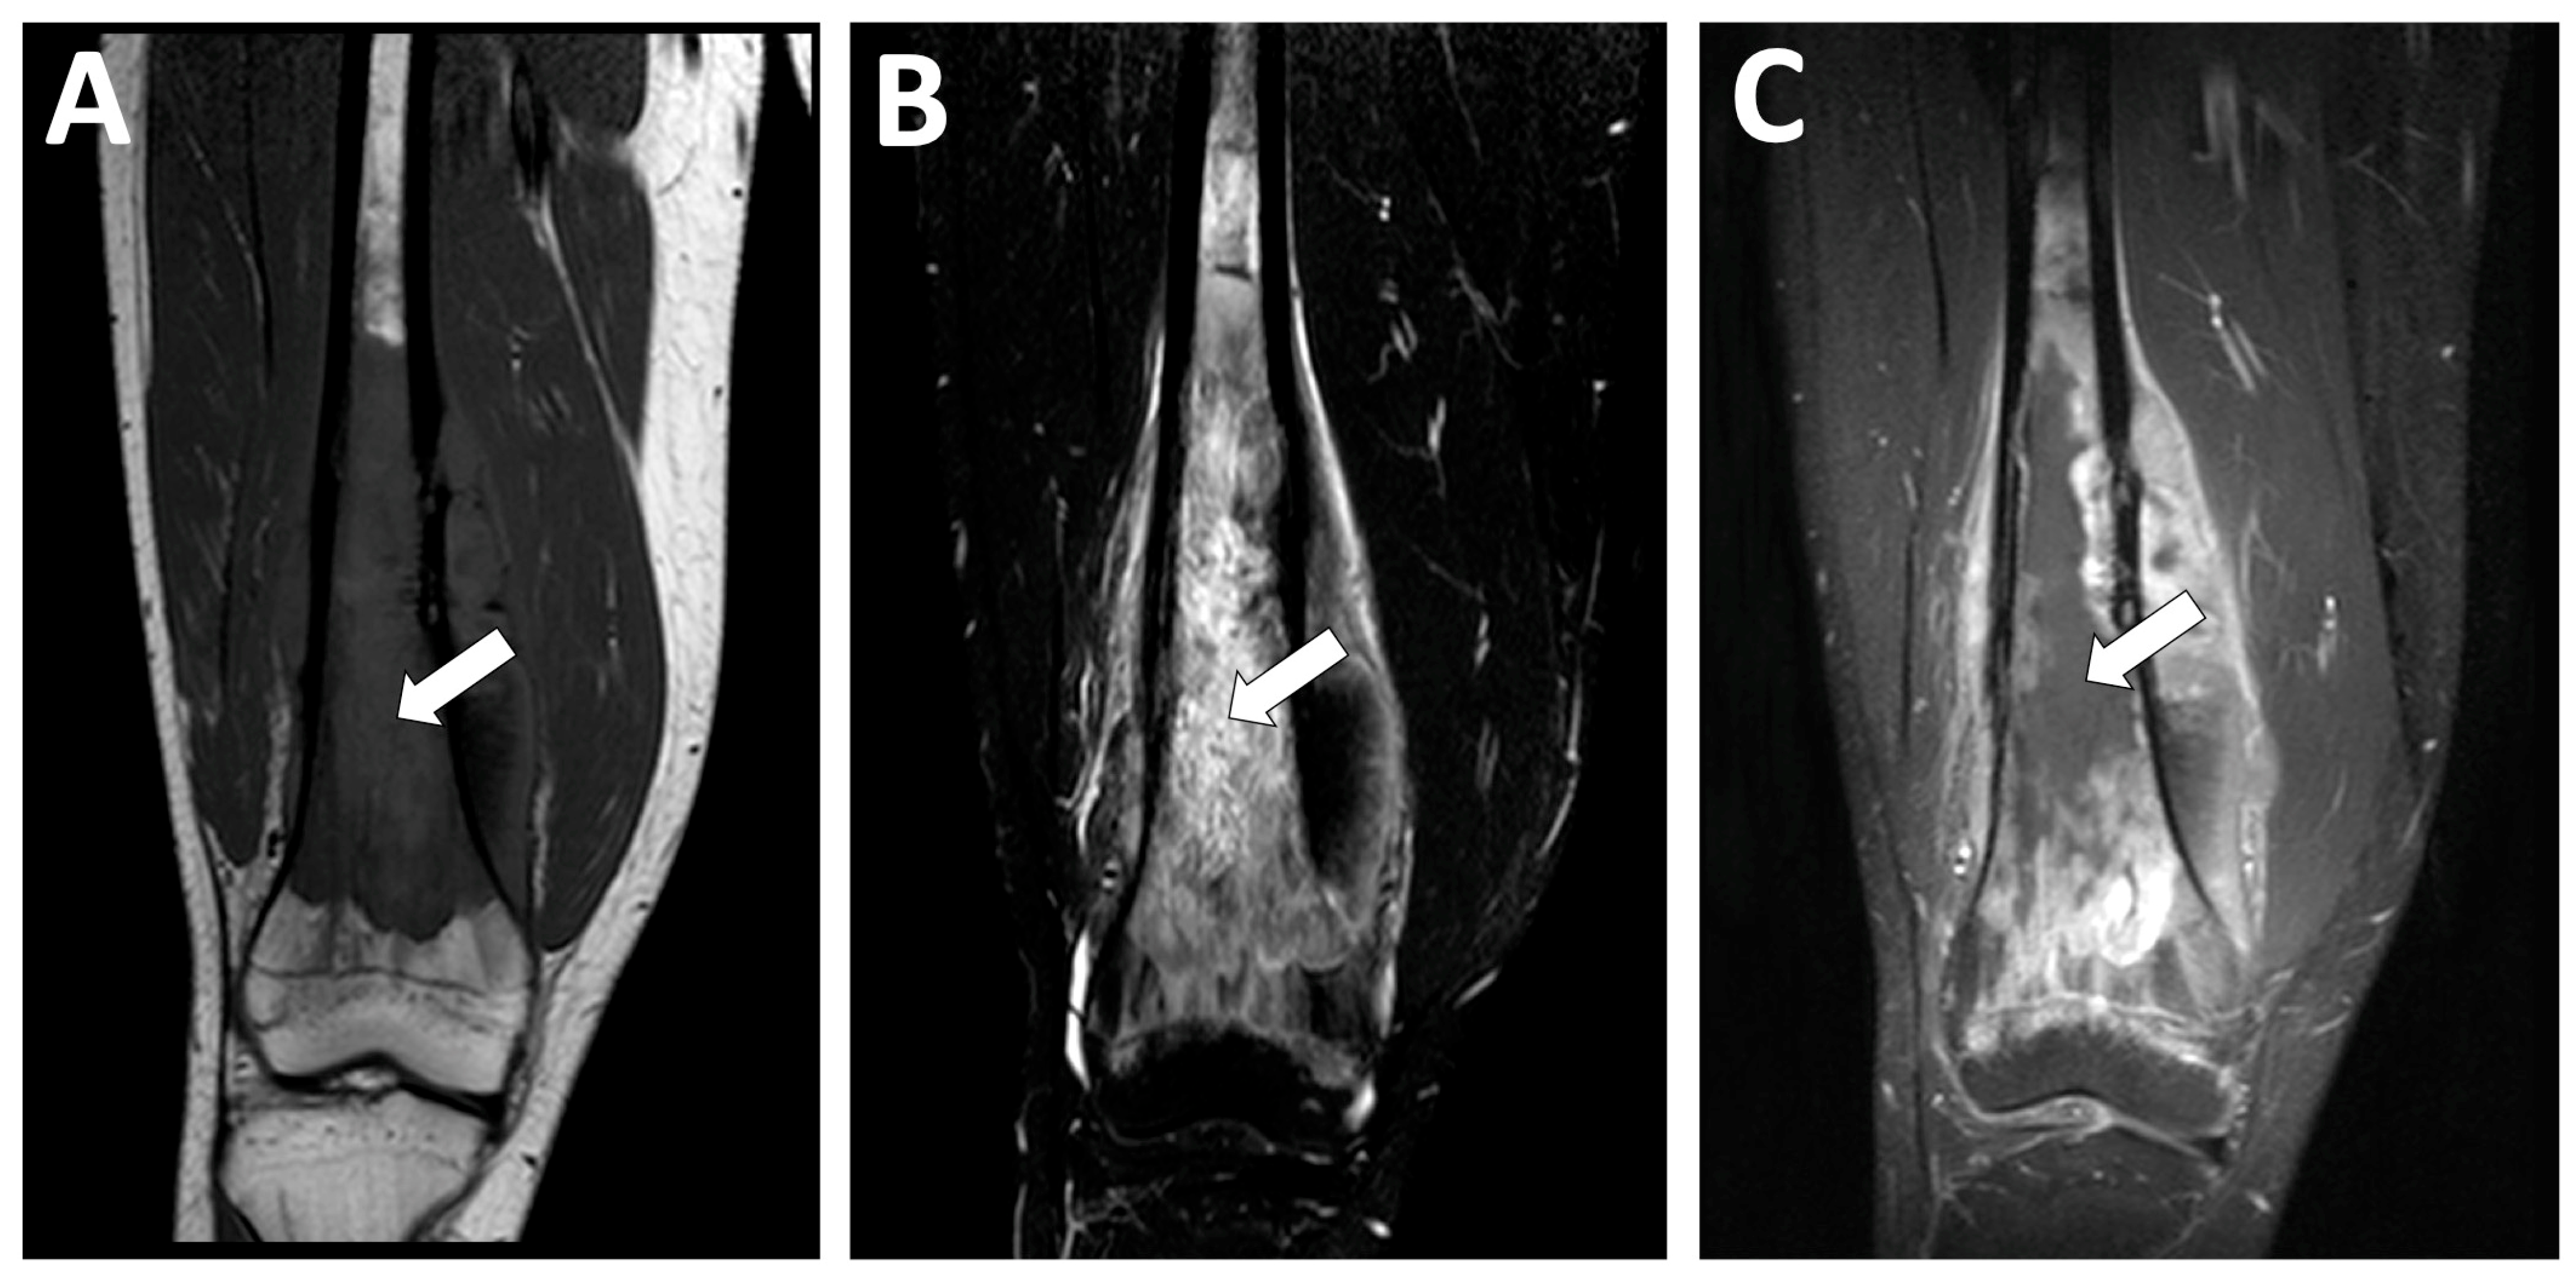

| Telangiectatic | Purely osteolytic | None or thin regular | Multicystic pattern with fluid–fluid levels and solid components on MRI |

| - MRI signal of internal hemorrhagic areas * | - Decreased OS |